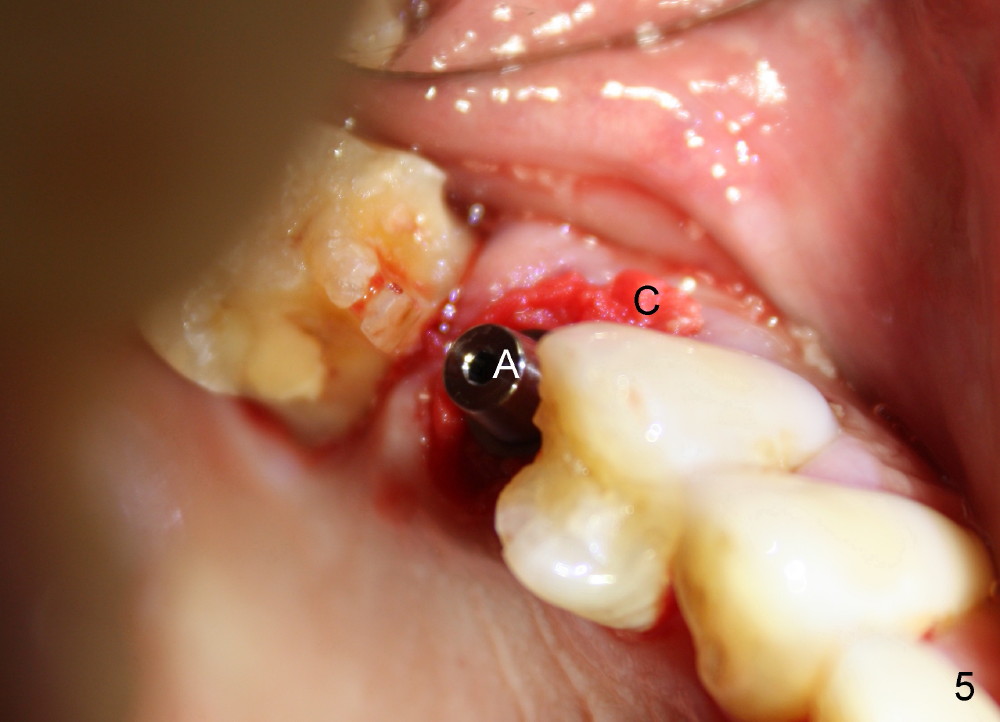

A 72-year-old man is a bruxer with #3 cusp fracture with chronic periapical radiolucency (Fig.1 *) and #4 acute crack.  It appears reasonable to take care of emergency (#4 extraction and immediate implant (Fig.3-7: 4.5x20 mm, 45 Ncm)) followed by root canal therapy or extraction for #3.  Eight (Fig.8) and 14 (Fig.9-11) days postop, the patient is doing fine and the wound heals normally.  But he does not agree any treatment for #3, since it is asymptomatic in spite of a fistula associated with the tooth (Fig.8,9 >).  Three months postop, the patient is still asymptomatic and is ready for #4 restoration since the tooth #28 cracks.  Follow-up PA shows the persistent distal gap (Fig.12 >, as compared to Fig.4), accompanied with crestal bone resorption (*).  Clinically the implant has mild mobility and light tenderness. The patient still refuses #3 treatment. It appears that the implant has failed to osteointegrate.  In brief, do not place an immediate implant next to active infection.